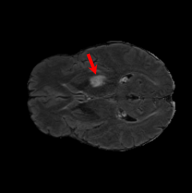

To see when and how X-Diffusion fails, we conducted an experiment on healthy brains (no tumour) using IXI dataset, by running an X-diffusion trained on BRATS brain tumor dataset. Our X-Diffusion achieved a PSNR of 35.86 dB on the IXI dataset despite being trained on the BRATS dataset. We then ran the tumour segmenter on the set of 582 healthy scans and corresponding generated MRIs. The segmenter predicted tumours in 9.9% of the real healthy brains and in 11.3% of the generated brain MRIs. Some of these tumor hallucination examples fron X-Diffusion generation are shown in Figure 10.

| Hallucination | Reference | Hallucination | Reference | Failure | Reference |

This shows how the generated MRIs indeed preserve the tumour information and can act as an affordable and informative pseudo-MRI, before conducting an actual costly MRI examination in hospitals. Given that our model has been trained on brain scans all with tumours, we expect to see hallucinations of tumours in healthy scans. We report two cases of failure of our model in Figure VII. Hallucinations of tumours on healthy samples represent 2% of the test set.